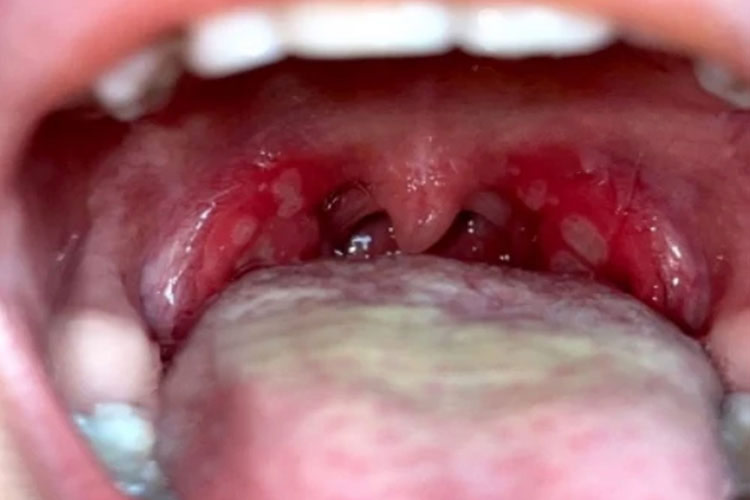

咽峡炎疱疹即疱疹性咽峡炎,主要表现为口腔黏膜出现灰白色疱疹,周围绕以红晕,疱疹可破溃形成溃疡,伴随急性发热。

患者咽部充血,口腔黏膜可出现数个小的灰白色疱疹,周围绕以红晕。2~3日后红晕加剧并扩大,疱疹破溃形成黄色溃疡。